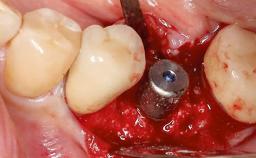

A 79-year-old female patient was referred to the Department of Periodontology of the University of Bern, Switzerland by her private dentist in May 2019. She had been rehabilitated in May 2005 with two tissue-level implants (Institut Straumann AG, Basel Switzerland) at sites 13 and 15, supporting a three-unit cemented fixed dental prosthesis (FDP). The metal-ceramic FDP had been cemented permanently with a glass-ionomer cement (Ketac Cem; 3M ESPE, Seefeld, Germany). Implant 13 had been diagnosed with peri-implant mucositis by the referring dentist in the course of regular supportive therapy. The patient was in good general health, did not smoke, and exhibited good self-performed plaque control.